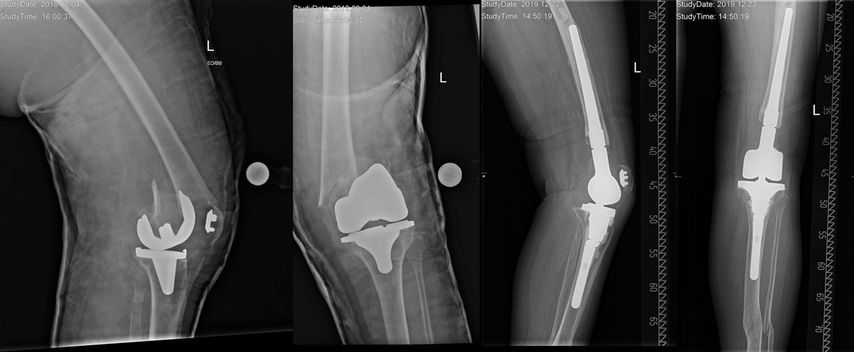

Abb. 1: Periprothetische Tibiafraktur vom Typ II nach Felix et al. (Mayo-Klassifikation). Die Autoren versorgten diese Fraktur mittels proximalen Tibiaersatzes sowie armierter Patellarsehne und führten einen kompletten Systemwechsel durch